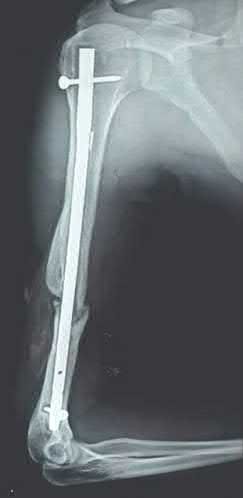

Question 19

A 28-year-old male sustains a closed comminuted tibial shaft fracture.

Two hours post-injury, he develops severe leg pain unyielding to narcotics. His blood pressure is 120/80 mmHg. Intracompartmental pressure monitoring is performed. Based on current guidelines, which measurement dictates an emergent 4-compartment fasciotomy?

Explanation

Acute compartment syndrome is classically defined by tissue hypoperfusion. The absolute compartment pressure is less reliable than the differential pressure (Delta P). A Delta P (Diastolic Blood Pressure minus Compartment Pressure) of less than 30 mmHg is an absolute indication for emergency fasciotomy, as capillary perfusion gradient is lost when tissue pressure approaches the diastolic pressure.